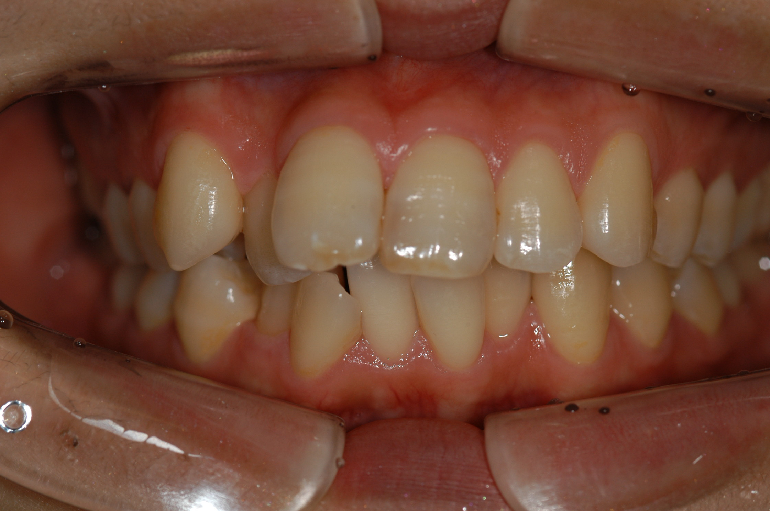

成人矯正症例紹介(主に12歳以降で永久歯が生え揃った状態の治療)

Vol.1

Before

治療前。

After

治療終了後。